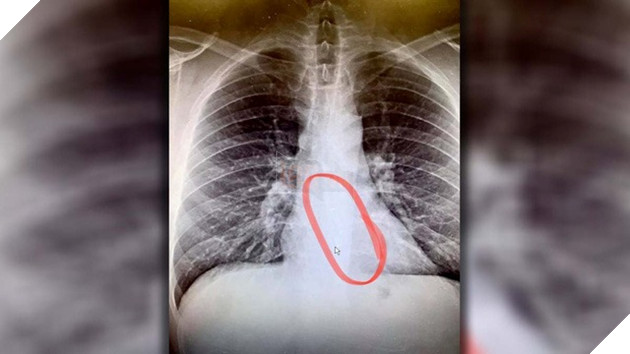

Sau khi tiến hành chụp CT, các bác sĩ đã xác định nhanh vị trí của chiếc AirPods Pro và điều đáng lo ngại đó là nó đã bị mắc kẹt ở một vị trí nguy hiểm. Thậm chí các bác sĩ còn lo ngại rằng nó có thể sẽ trôi sâu hơn và phải thực hiện gấp một thủ tục phẫu thuật xâm lấn hơn để có thể lấy chiếc AirPods ra ngoài.